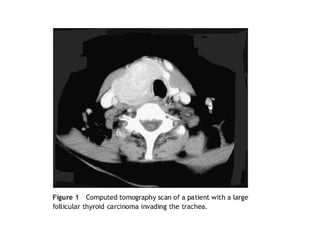

   Complejo laringo-traqueal

   Síntomas en 28% afección laríngea y 18% traqueal.

   Se presenta disnea cuando la luz de la tráquea se

reduce más del 50%.

   La enfermedad puede invadir la vía aérea ya sea

directamente por el tumor o por invasión extra-

ganglionar.

• 22.

Complejo laringo-traqueal  Síntomas en 28% afección laríngea y 18% traqueal.  Se presenta disnea cuando la luz de la tráquea se reduce más del 50%.  La enfermedad puede invadir la vía aérea ya sea directamente por el tumor o por invasión extra- ganglionar.